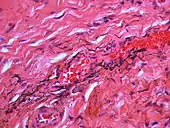

If necessary, the diagnosis can be confirmed histologically by excisional biopsy, which excludes nevi and melanomas.[3]:138 If a biopsy is taken, the histopathologic appearance is:[1]

- Pigmented fragments of metal within connective tissue

- Staining of reticulin fibers with silver salts

- A scattered arrangement of large, dark, solid fragments or a fine, black or dark brown granules

- Large particles may be surrounded by chronically inflamed fibrous tissue

- Smaller particles surrounded by more significant inflammation, which may be granulomatous or a mixture of lymphocytes and plasma cells